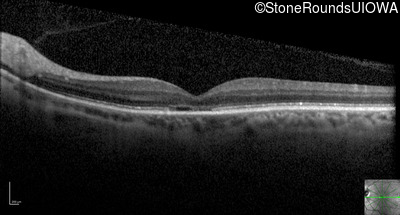

Optical Coherence Tomography - Right - 20/100

Exemplar / OCT Stack

OCT Stack